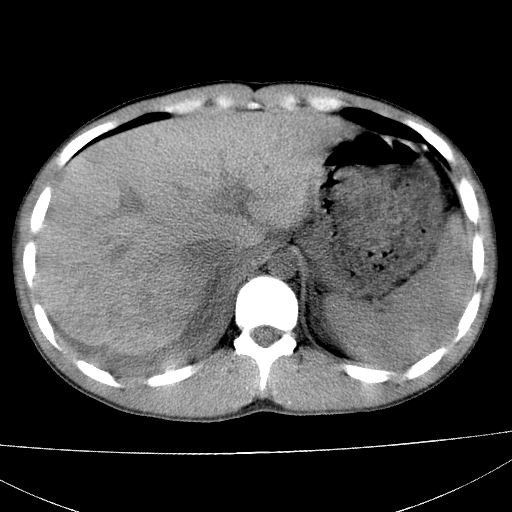

标题: CT15860:男,21岁,腹部外伤2小时伴胸疼。 [打印本页]

标题: CT15860:男,21岁,腹部外伤2小时伴胸疼。

b超示:肝破裂。

肝脏及肾脏明显有损伤性改变并激发腹腔内积液(血),以肝脏撕裂及肾周积血显著。

1)肝破裂伴腹腔积液(血)。2)右肾破裂伴右肾包膜下及肾周血肿。3)腹部空腔脏器穿孔可能。4)右侧少量胸腔积液(血)。